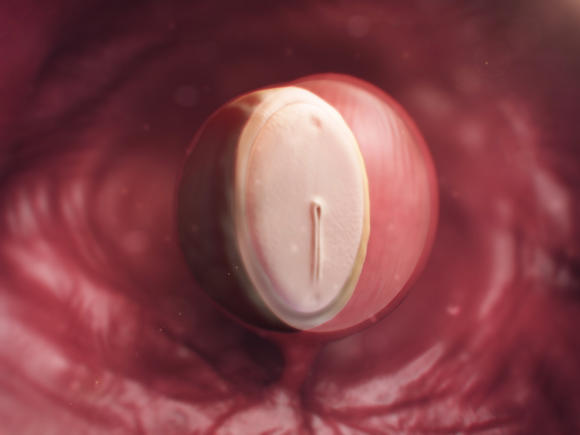

3-4 வாரம்

கருத்தரித்து வெறும் மூன்று வாரம் 18 – வது நாளில் குழந்தையின் இதயம் தோன்றுகிறது. 3 வாரம் 1 நாள் கழிந்து இதயம் துடிக்கத் துவங்குகிறது. இச்சமயத்தில் கருத்தரித்த குழந்தையின் இதயம் நிமிடத்திற்க்கு 105 – 120 முறை துடிப்பதாக ஆய்வாளர்கள் ஆதாரப்பூர்வமாக நிரூபித்துள்ளனர்.